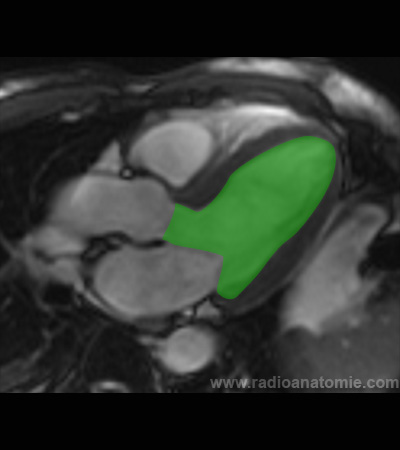

Radioanatomie et plans de coupe en IRM cardiaque

Ventricule gauche